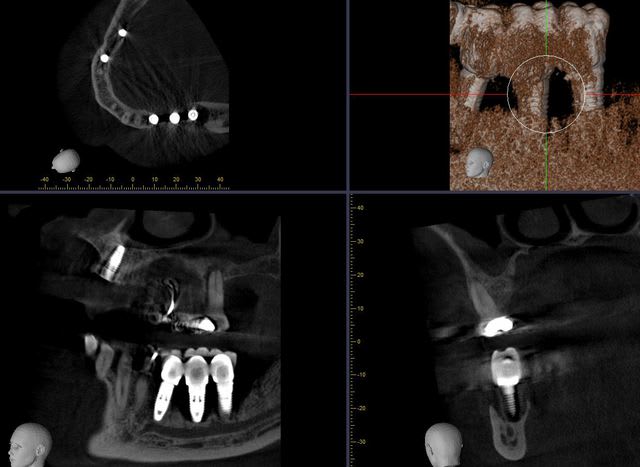

le même patient

le pauvre, il est vraiment mal tombé...

oui! c'est juste! mais le filtre n'était pas très bon et les réglages de départ non plus...et là, c'est pas la qualité de l'image qui est intéressante mais la position irréaliste des implants.

11 et 21 sortent à 4mm de la crête osseuse et dans la gencive libre...